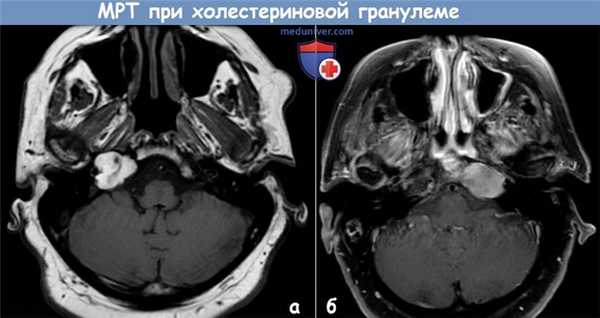

Manasse описал случай «грануляционной опухоли с гигантскими клетками инородных тел» верхушки пирамиды височной кости еще в 1894 году. С тех пор для их описания используется термин «холестериновая» или «холестероловая» гранулема.

Холестериновая гранулема является наиболее распространенным образованием верхушки пирамиды, с которым отиатры сталкиваются в своей работе. Существует несколько предполагаемых механизмов их формирования. Вторым по частоте встречаемости образованием является холестеатома. Далее мы рассмотрим патогенез этих двух образований.

Холестериновая гранулема может выглядеть как грануляционная ткань или как коричневая, зеленая или ярко-желтая киста. Образование холестеатомы из холестериновой кисты невозможно.